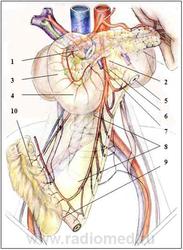

Наименее фиксированными к поджелудочной железе, т.е. наиболее подвижными, лежащими внутрибрюшинно, являются: луковица ДПК, имеющая рыхлую клетчатку на задней стенке и дуоденоеюнальный переход, также имеющий сзади рыхлую клетчатку (рис. 2.2). Данные образования имеют собственные связки, обеспечивающие им подвижность.

Рисунок 2.2. Хирургическая анатомия двенадцатиперстной кишки

1-луковица ДПК

2-дуоденоеюнальный переход

3-нисходящая часть ДПК

4-нижнегоризонтальная часть ДПК

5-начальные отделы тонкой кишки

6-верхняя брыжеечная артерия

7-верхняя брыжеечная вена

8-Корень брыжейки тонкой кишки

9-илеоцекальный переход

10-восходящая ободочная кишка